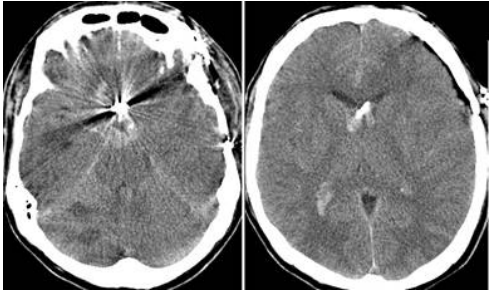

11 60 歲蕭先生早上六點起床後發現左側無力,隔日因意識不清被家人送至急診,於急診時右側瞳孔已 呈現放大且無反射,電腦斷層檢查如下圖,下列何項處置對蕭先生並無幫助?

(A)給予 mannitol (B)施打靜脈血栓溶解劑(intravenous tissue plasminogen activator) (C)氣管內管插管併給予過度換氣(hyperventilation) (D)施行顱骨切除術(craniectomy)